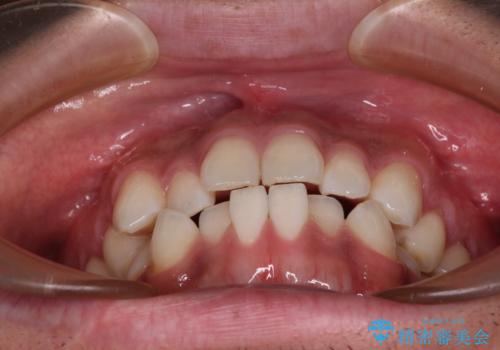

目立たない装置でデコボコを改善 ハーフリンガルによる矯正治療

- 上下顎歯列のデコボコを改善したいとのことで来院された患者様です。

自己管理の大変なインビザラインや、目立つ表側のワイヤー矯正は避けたいとのことで、

上顎だけ裏側装置のハーフリンガルにて矯正しました。

一年と数か月で矯正を終えることができました。